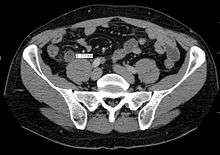

Computed tomography

Where it is readily available, computed tomography (CT) has become frequently used, especially in people whose diagnosis is not obvious on history and physical examination. Concerns about radiation tend to limit use of CT in pregnant women and children, especially with the increasingly widespread usage of MRI.[47][48]

The accurate diagnosis of appendicitis is multi-tiered, with the size of the appendix having the strongest positive predictive value, while indirect features can either increase or decrease sensitivity and specificity. A size of over 6 mm is both 95% sensitive and specific for appendicitis.[49]

However, because the appendix can be filled with fecal material, causing intraluminal distention, this criterion has shown limited utility in more recent meta analyses.[50] This is as opposed to ultrasound, in which the wall of the appendix can be more easily distinguished from intraluminal feces. In such scenarios, ancillary features such as increased wall enhancement as compared to adjacent bowel and inflammation of the surrounding fat, or fat stranding, can be supportive of the diagnosis, although their absence does not preclude it. In severe cases with perforation, an adjacent phlegmon or abscess can be seen. Dense fluid layering in the pelvis can also result, related to either pus or enteric spillage. When patients are thin or younger, the relative absence of fat can make the appendix and surrounding fat stranding difficult to see.[50]